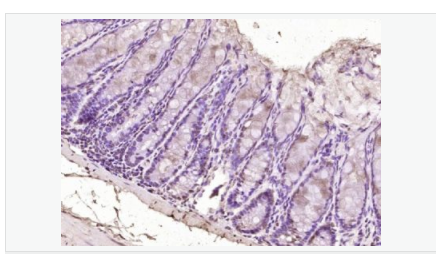

| 產(chǎn)品應(yīng)用 | ELISA=1:5000-10000 IHC-P=1:100-500 IHC-F=1:100-500 ICC=1:100-500 IF=1:100-500 (石蠟切片需做抗原修復(fù)) not yet tested in other applications. optimal dilutions/concentrations should be determined by the end user. |

| 產(chǎn)品介紹 | Sox genes comprise a family of genes that are related to the mammalian sex determining gene SRY. These genes similarly contain sequences that encode for the HMG-box domain, which is responsible for the sequence-specific DNA-binding activity. Sox genes encode putative transcriptional regulators implicated in the decision of cell fates during development and the control of diverse developmental processes. The highly complex group of Sox genes cluster at least 40 different loci that rapidly diverged in various animal lineages. At present, 30 Sox genes have been identified. Members of this family have been shown to be conserved during evolution and to play key roles during animal development. Some are involved in human diseases, including sex reversal. Function: Transcriptional repressor. Binds to the DNA sequence 5'-AACAAT-3'. Subunit: Interacts with CTNNB1/beta-catenin; this interaction may lead to the proteasomal degradation of active CTNNB1 and thus inhibition of Wnt/beta-catenin-stimulated transcription. Subcellular Location: Nucleus. Tissue Specificity: Widely expressed in adult and fetal tissues. Present both in mesenchymal and epithelial cells in some adult tissues, including colon. Tends to be down-regulated in prostate adenocarcinomas and colorectal tumors due to promoter hypermethylation. Similarity: Contains 1 HMG box DNA-binding domain. Contains 1 Sox C-terminal domain. SWISS: Q9BT81 Gene ID: 83595 Database links: Entrez Gene: 83595 Human Entrez Gene: 20680 Mouse Entrez Gene: 378665 Xenopus laevis Omim: 612202 Human SwissProt: Q9BT81 Human SwissProt: P40646 Mouse SwissProt: O42342 Xenopus laevis Unigene: 709543 Human Unigene: 42162 Mouse Unigene: 1241 Xenopus laevis Important Note: This product as supplied is intended for research use only, not for use in human, therapeutic or diagnostic applications. |